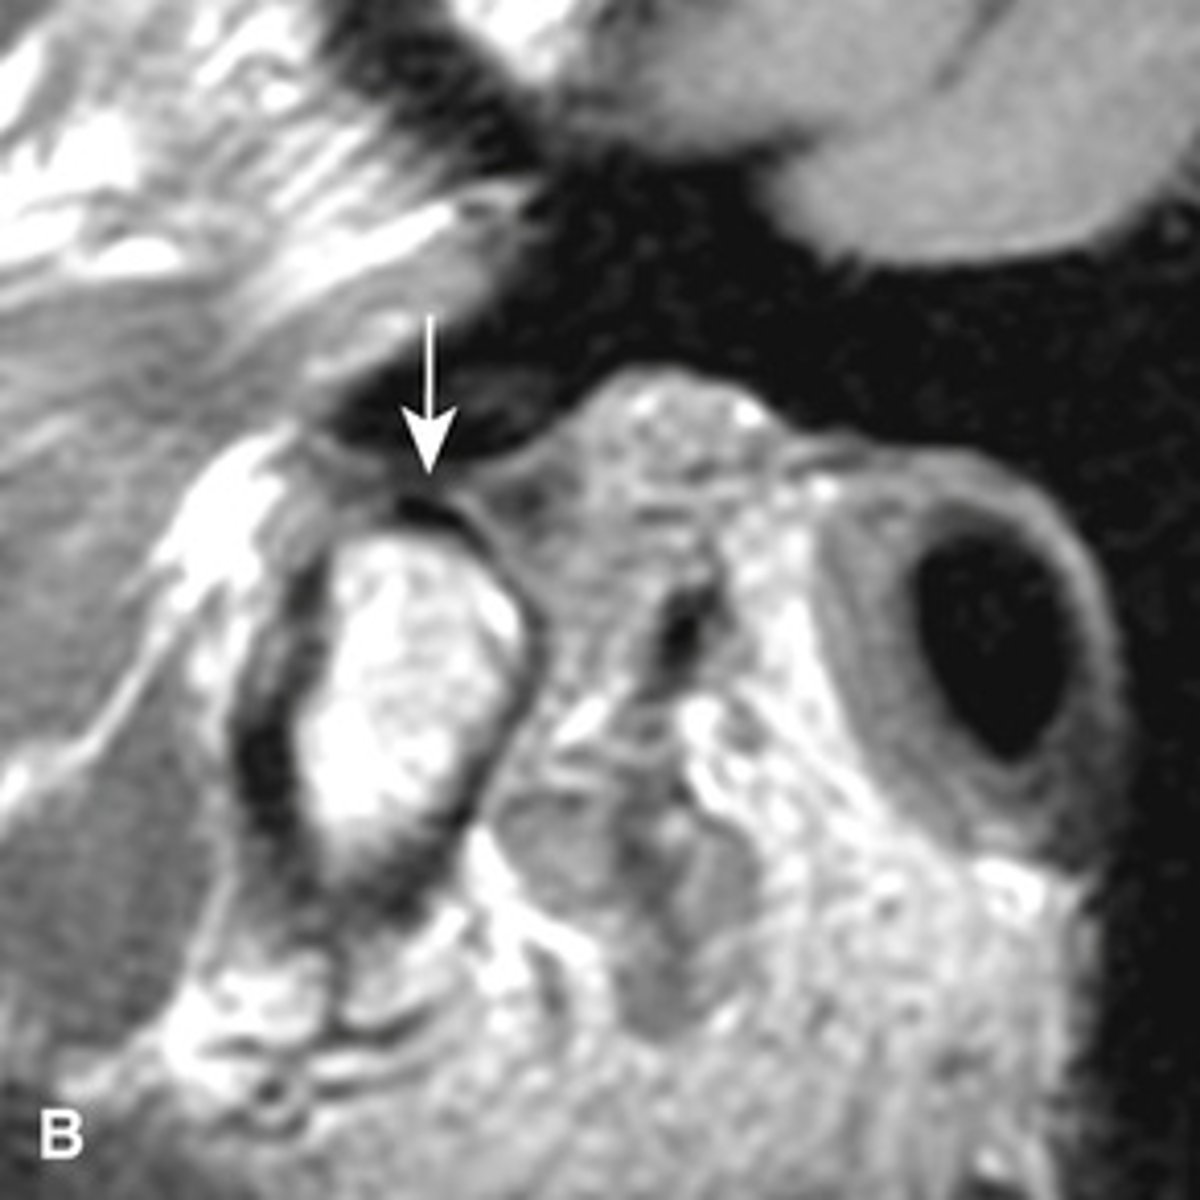

MRI image of the TMJ allowing for visualization of the condylar disc.

What is the image showing?

anteriorly displaced (the posterior band is anterior to the condyle)

The MRI is showing the disc ________ ______